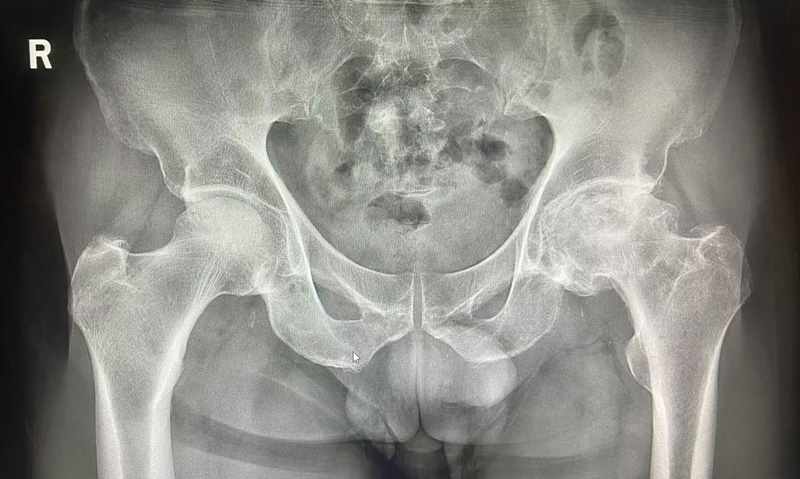

2025-11-14近日,骨科在麻醉科的协助下,成功完成我院首例左股骨头缺血性坏死全髋关节置换术。患者为中年男性,四年前出现双髋部疼痛,以左侧为著,行走约300米后疼痛即加重。曾在当地医院就诊,对症治疗效果不佳,于11月3日来到我院就诊并接受治疗。

全髋关节置换术是治疗终末期髋关节疾病的有效方法,能够显著缓解疼痛、改善关节功能,提高患者的生活质量。我院首例全髋置换术的成功开展,为本地及周边地区的髋关节疾病患者带来了福音。